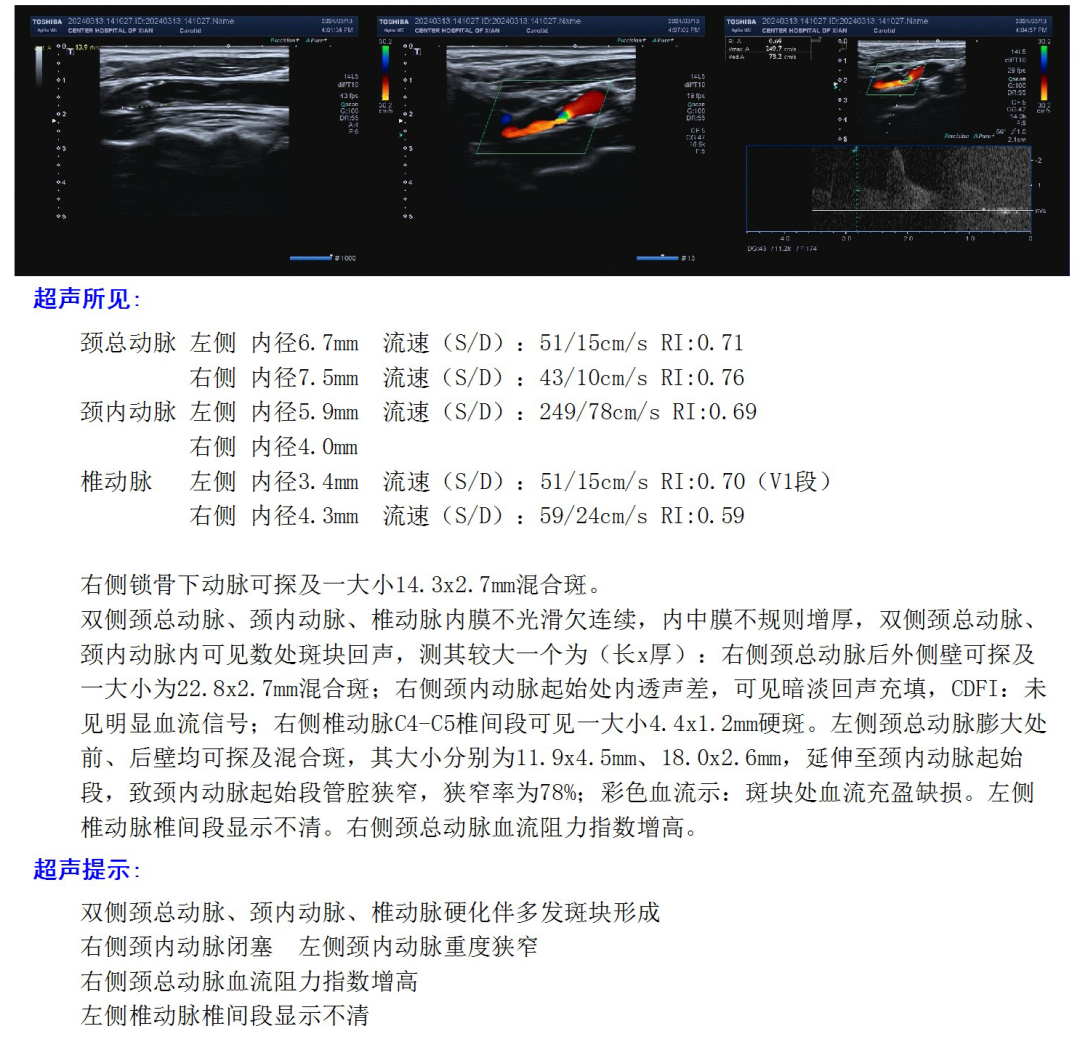

颈动脉超声

双侧股动脉造影:双侧髂动脉支架迂曲,不能通过造影导管及导丝。

右侧颈内动脉闭塞。

左侧颈内动脉重度狭窄,左侧大脑中动脉闭塞,通过前交通动脉向右侧大脑中动脉供血区代偿。